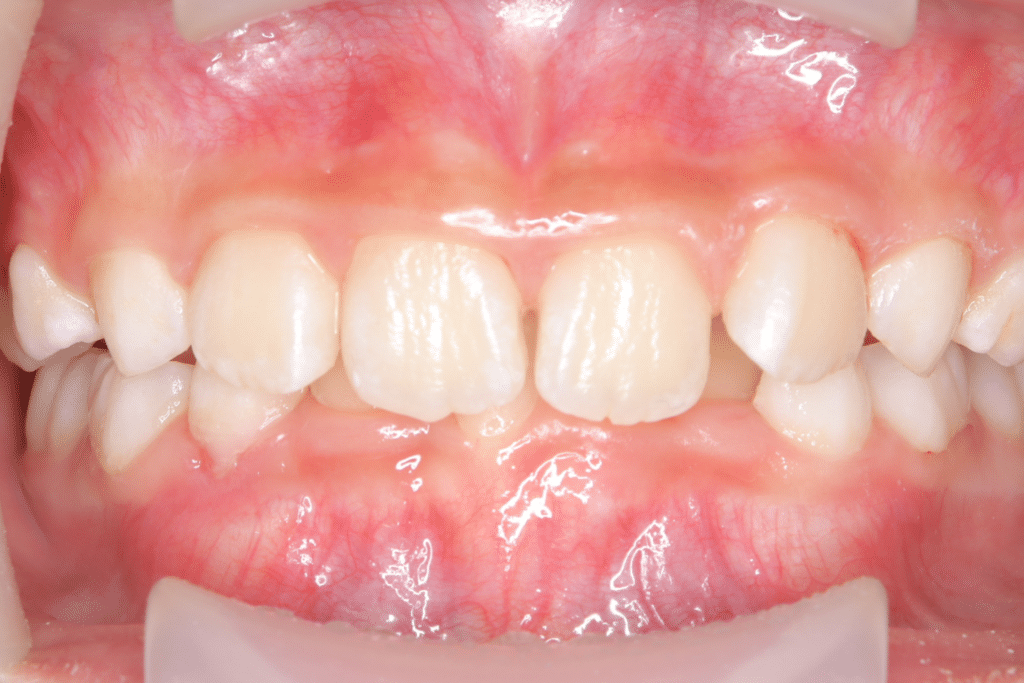

過蓋咬合

(9歳5ヶ月)

開始後3ヶ月

(開始後3ヶ月目)このあたりからマウスピース使用時間は起きてる時最大で120分が可能となった。目標は「起きている時60分以上+就寝時も使用」とし、筋機能トレーニングも併用開始。